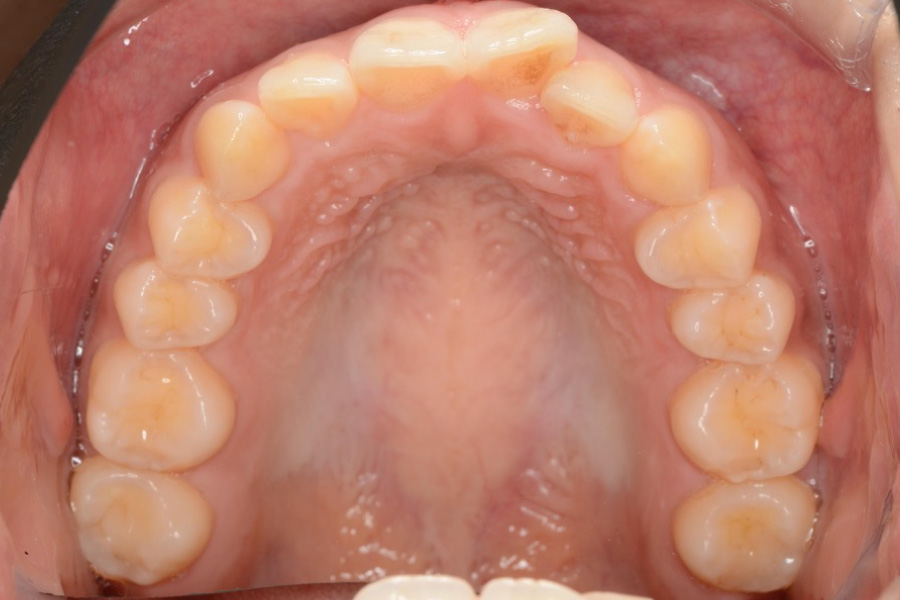

【20代女性】

全体のガタつきを

インビザライン矯正で治療したケース

治療後

主訴 全体のガタつきが気になる

治療内容 インビザライン矯正

非抜歯